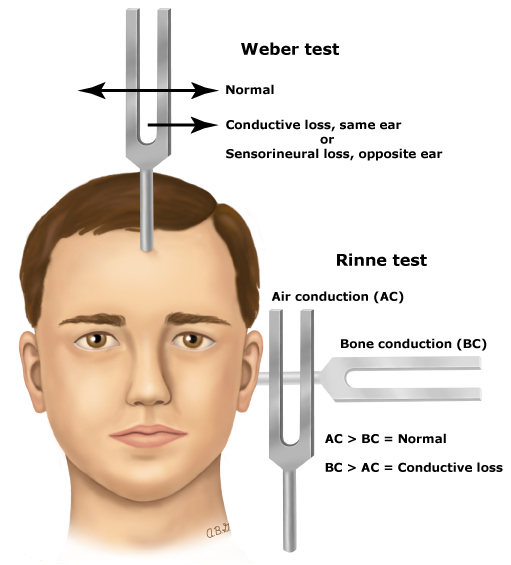

♦ weber and rinne test (વેબર અને રિન ટેસ્ટ)

◘ Bone conduction hearing test : =

Rinne Test-રિન ટેસ્ટ

- આ ટેસ્ટમાં વાઇબ્રિટીંગ ટ્યુનિક ફોર્ક ને ઈયર ની પાછળ mastoid process પર પ્લેસ કરવામાં આવે છે માસ્ટરોઈડ પ્રોસેસ ઉપર જો પેશન્ટની વાઇબ્રેશન લાંબા સમય સુધી ફીલ ન થાય તો ટયુનિક ફોર્ક ને ઈયરની આગળ બાજુ રાખવામાં આવે છે જો પેશન્ટ એ રિંગિંગ સાઉન્ડ સાંભળવા માટે એબલ ન હોય તો તે કાનમાં પેશન્ટને કંડક્ટિવ હેરિંગ લોસ છે તેમ કહી શકાય.

weber Test-વેબર

વધારેમાં ટ્યુનિક ફોર્ક ને ફોરહેડ પર રાખવામાં આવે છે.પછી પેશન્ટને પૂછવામાં આવે છે કે અવાજ એ ફોરહેડના વચ્ચેના ભાગમાં hearing થાય છે કે નહીં.અથવા બંને કાનમાં જોરથી અવાજ સંભળાય છે.

- જો પેશન્ટ ને conductive hearing loss હશે તો અફેક્ટેડ કાનમાં વધુ અવાજ સંભળાશે.

- જો પેશન્ટ ને sensorineural hearing loss તો તે કાનમાં ઓછો અવાજ સંભળાશે.

- આ ટેસ્ટ એ ઓડિયોલોજીસ્ટ ને કયા પ્રકારનું લોસ છે તે હશે જ કરવા માટે કરવામાં આવે છે.

- In conductive hearing loss ( caused by problem in the outer or middle ear),

- In sensorineural hearing loss ( caused by problem in the cochlea, the sensory organ of hearing)

- Or neural ( caused by a problem in the auditory nerve or auditory pathway of the brain).